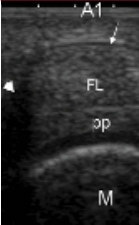

DIAGNOSING TRIGGER FINGER

Trigger finger will start as just a little swelling or an inability to fully bend the fingers or fully straighten them. This is because swelling starts to settle in the knuckles of the fingers around the A1 or first pulley in the hand. The knuckles need to be stable and in some cases especially repetitive gripping a person might lose this stability and then become swollen and develop a trigger finger.